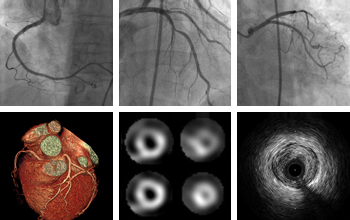

협심증이란 협착증으로 인해서 혈액 공급이 순탄하게 되지 못하고 가만히 있을 때에는 모르고 있다가 계단을 걸어서 올라가거나, 무거운 짐을 들고 이동하는 경우, 그리고 과식을 하고 난 뒤에 심장 근육이 일을 많이 하게 만드는 경우가 있을 때에 가슴통증이 생기는 것으로 알 수 있어요. 하지만 가만히 있다면 아무이 없다고 느끼실 수 있습니다. 하지만 심근경색 이란 관상동맥에 협착증으로 이어지게 됩니다.

갑자기 관상동맥 내에 혈전이 발생하다 보면 기존에 좁아져 있던 협착증 부위가 생기다 보니, 혈액 공급이 차단이 되어 발생하는 이유가 크므로 협심증 증상과 연관이 없이 가만히 숨만 쉬고 있어도 통증이 누그러 들지 않고 지속이 계속된다고 느낄 수 있어요. 협심증 증상과 심근경색 증상이 다르다는 것을 알 수 있습니다. 그렇다면 협심증 증상은 가슴 통증 경우에는 주로 운동을 하고 있을 때 생기는 것으로 알려졌는데 가슴 좌측 또는 중앙부에서 뻐근한 통증이 발생합니다.

혈관 면적의 70%이상 좁아지면 협심증 증상이 생기게 되며 협심증은 서서히 진행되는 경우가 많아 초기에 증상을 뚜렷하게 알기 힘듭니다. 협심증은 심장에 혈류는 흐르므로 운동을 한 경우 혹은 추운 날씨에 노출되는 등 갑작스럽게 심장 근육의 산소 요구량이 증가하는 상황에서 나타납니다.

내피세포가 손상되어 기능이 저하되면 관상동맥을 흐르는 혈액에 포함된 혈소판과 대식세포가 활성화되어 만성 동맥경화증이 진행돼요. 이 협착으로 인해 관상동맥의 70% 이상이 막히게 되면 심근의 일부가 허혈 상태가 되어 관상동맥 혈류가 원활하지 않아 협심증이 생기게 돼요.